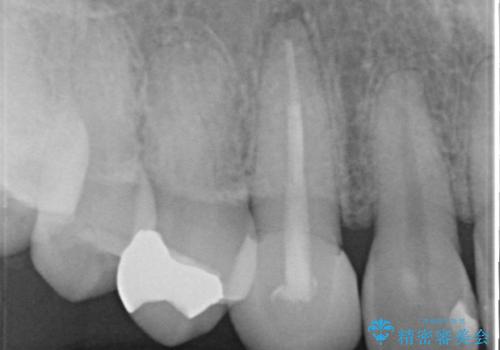

- 他院にて根管治療を行ったが疼きが治まらないため、当院にいらっしゃった方の症例です。

再根管治療を行い症状が治まったのを確認後、オールセラミッククラウン(スペシャル)による補綴を行いました。

- オールセラミッククラウン(スペシャル)…¥130,000、仮歯…¥10,000、ファイバーコア…¥20,000、精密根管治療費別途費用は治療当時の料金となります